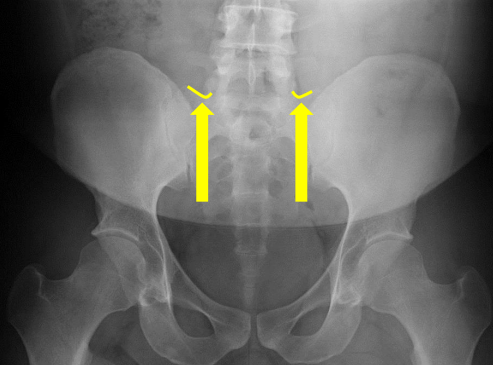

Femur heads

Superior iliac crests

S2 tubercle